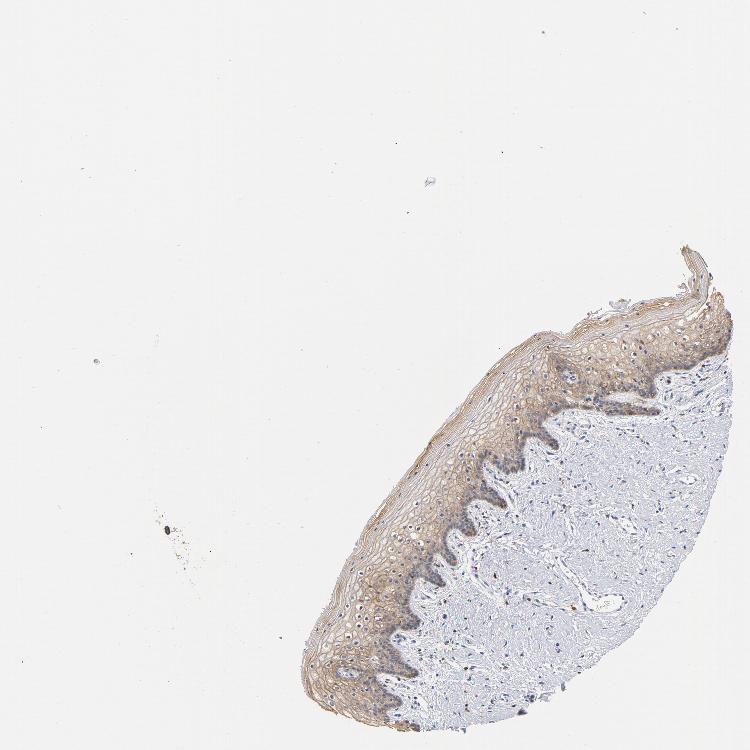

TISSUE PRIMARY DATA VAGINA Show tissue menu

VAGINA - Antibody stainingi

Antibody staining in the annotated cell types in the current human tissue is reported as not detected, low, medium, or high, based on conventional immunohistochemistry profiling in selected tissues. This score is based on the combination of the staining intensity and fraction of stained cells.

Each image is clickable and will lead to virtual microscopy that enables deeper exploration of all samples and also displays staining intensity scores, fraction scores and subcellular localization as well as patient and tissue information for each sample.

Antibody HPA021616Antibody CAB004035Antibody CAB075739

Squamous epithelial cells MediumLowNot detected